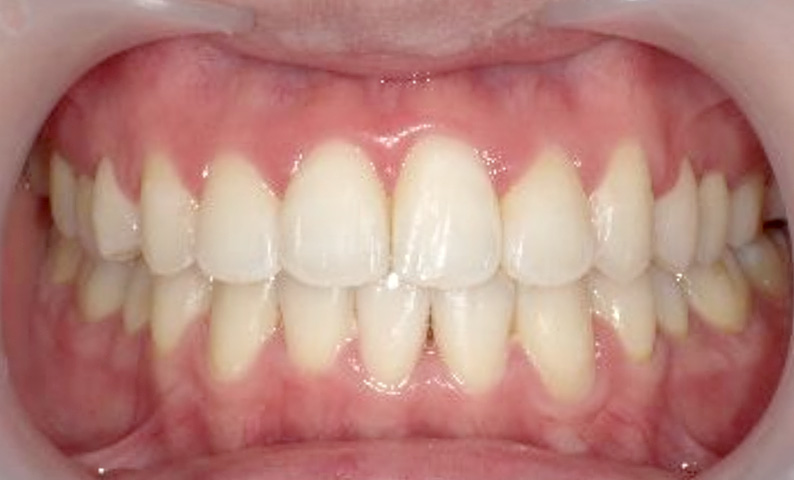

症例_001 上下顎の部分矯正

治療期間:10ヶ月金額:51万円+税女性八重歯前歯のガタガタ

| Before | After |

|---|---|

|